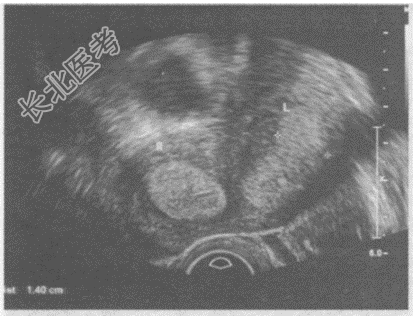

- 单项选择题临床资料:女性患者, 29岁,自诉月经不规律。

超声综合描述: 纵切面可见两个独立完整的子宫,均有完整的内膜、肌层、浆膜层, 内膜厚度1.4cm。横切面见两子宫间有凹陷,两宫体并列呈蝴蝶状, 宫颈及阴道完全分开。

超声提示: A、完全纵隔子宫

B、残角子宫

C、双子宫

D、双角子宫

E、鞍状子宫